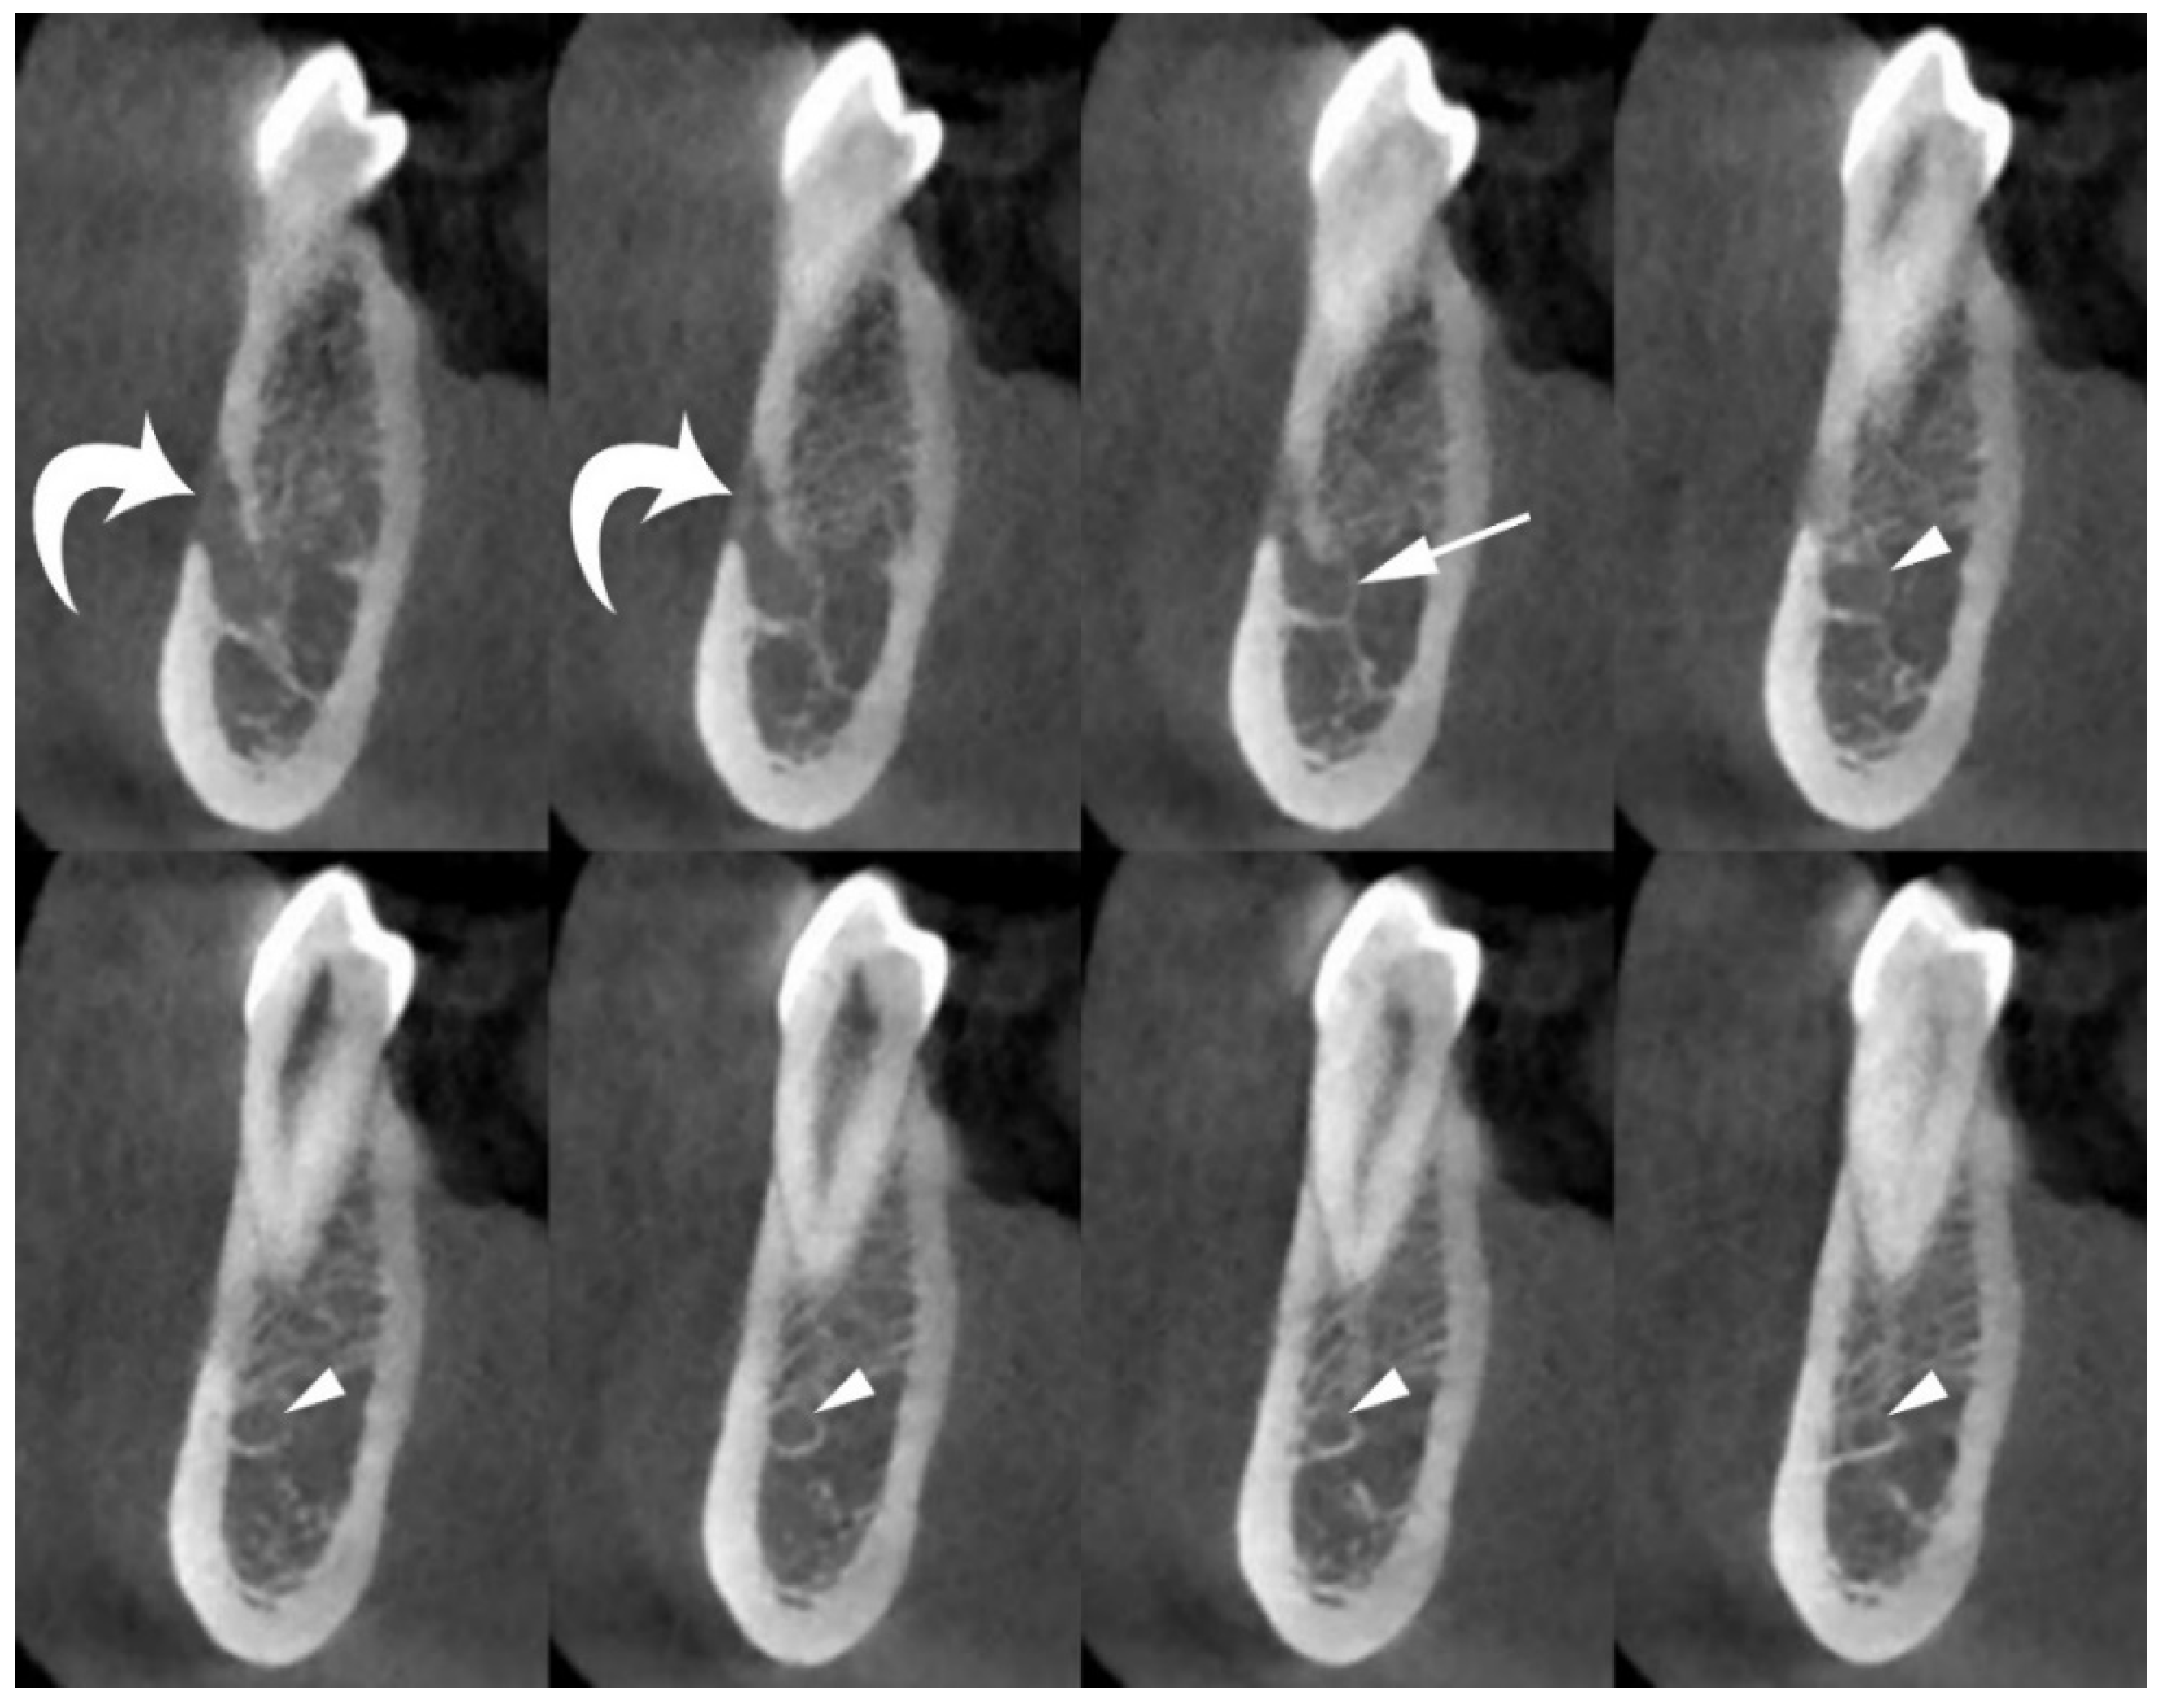

In clinical practice, the most commonly used radiological technique for morphological assessment of the MIC is cone-beam computed tomography (CBCT) [3,4,5,13,14,15,16,17,18,19,20,21,22,23] (Figure 1).

Figure 1.

Axial (top) and panoramic (bottom) cone-beam computed tomography (CBCT) images of the left hemi-mandible demonstrate that the mandibular incisive canal (MIC) (arrowheads) originates from the anterior loop of mandibular canal (arrows) and proceeds towards the midline below the apices of the teeth. The mental foramen (curved arrows), mandibular canal (wavy arrow), and mandibular foramen (asterisk) are also shown.